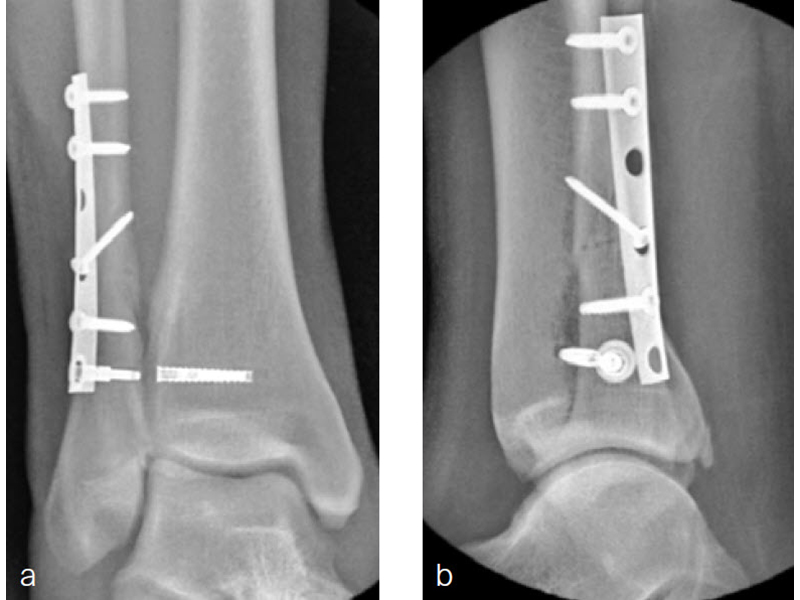

A 34-year-old woman was injured while riding a motor scooter sustaining an ankle fracture with associated syndesmotic injury (Fig 6a). The fibula was reduced anatomically and stabilized with a 1/3 tubular plate (Fig 6b). The unstable syndesmosis was reduced and provisionally stabilized with a K-wire and clamp (Fig 7) before FIBULINK Implant System implantation (Fig 8). The patient had an uneventful recovery (Fig 9).